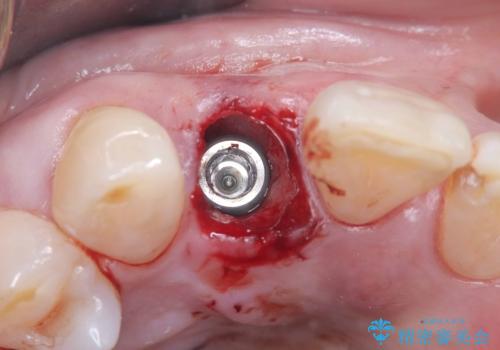

インプラント治療は、低侵襲で短期間に行える「抜歯即時インプラント治療」を選択しました。

この方法は、抜歯したその日にインプラントを埋入し、手術が1回で済むのが大きな特徴です。

治療期間も短く、抜歯からわずか3か月でオールセラミッククラウンを装着することができます。

また、オペ当日には仮歯まで装着するため、見た目を気にせず普段通りの生活を送ることができます。